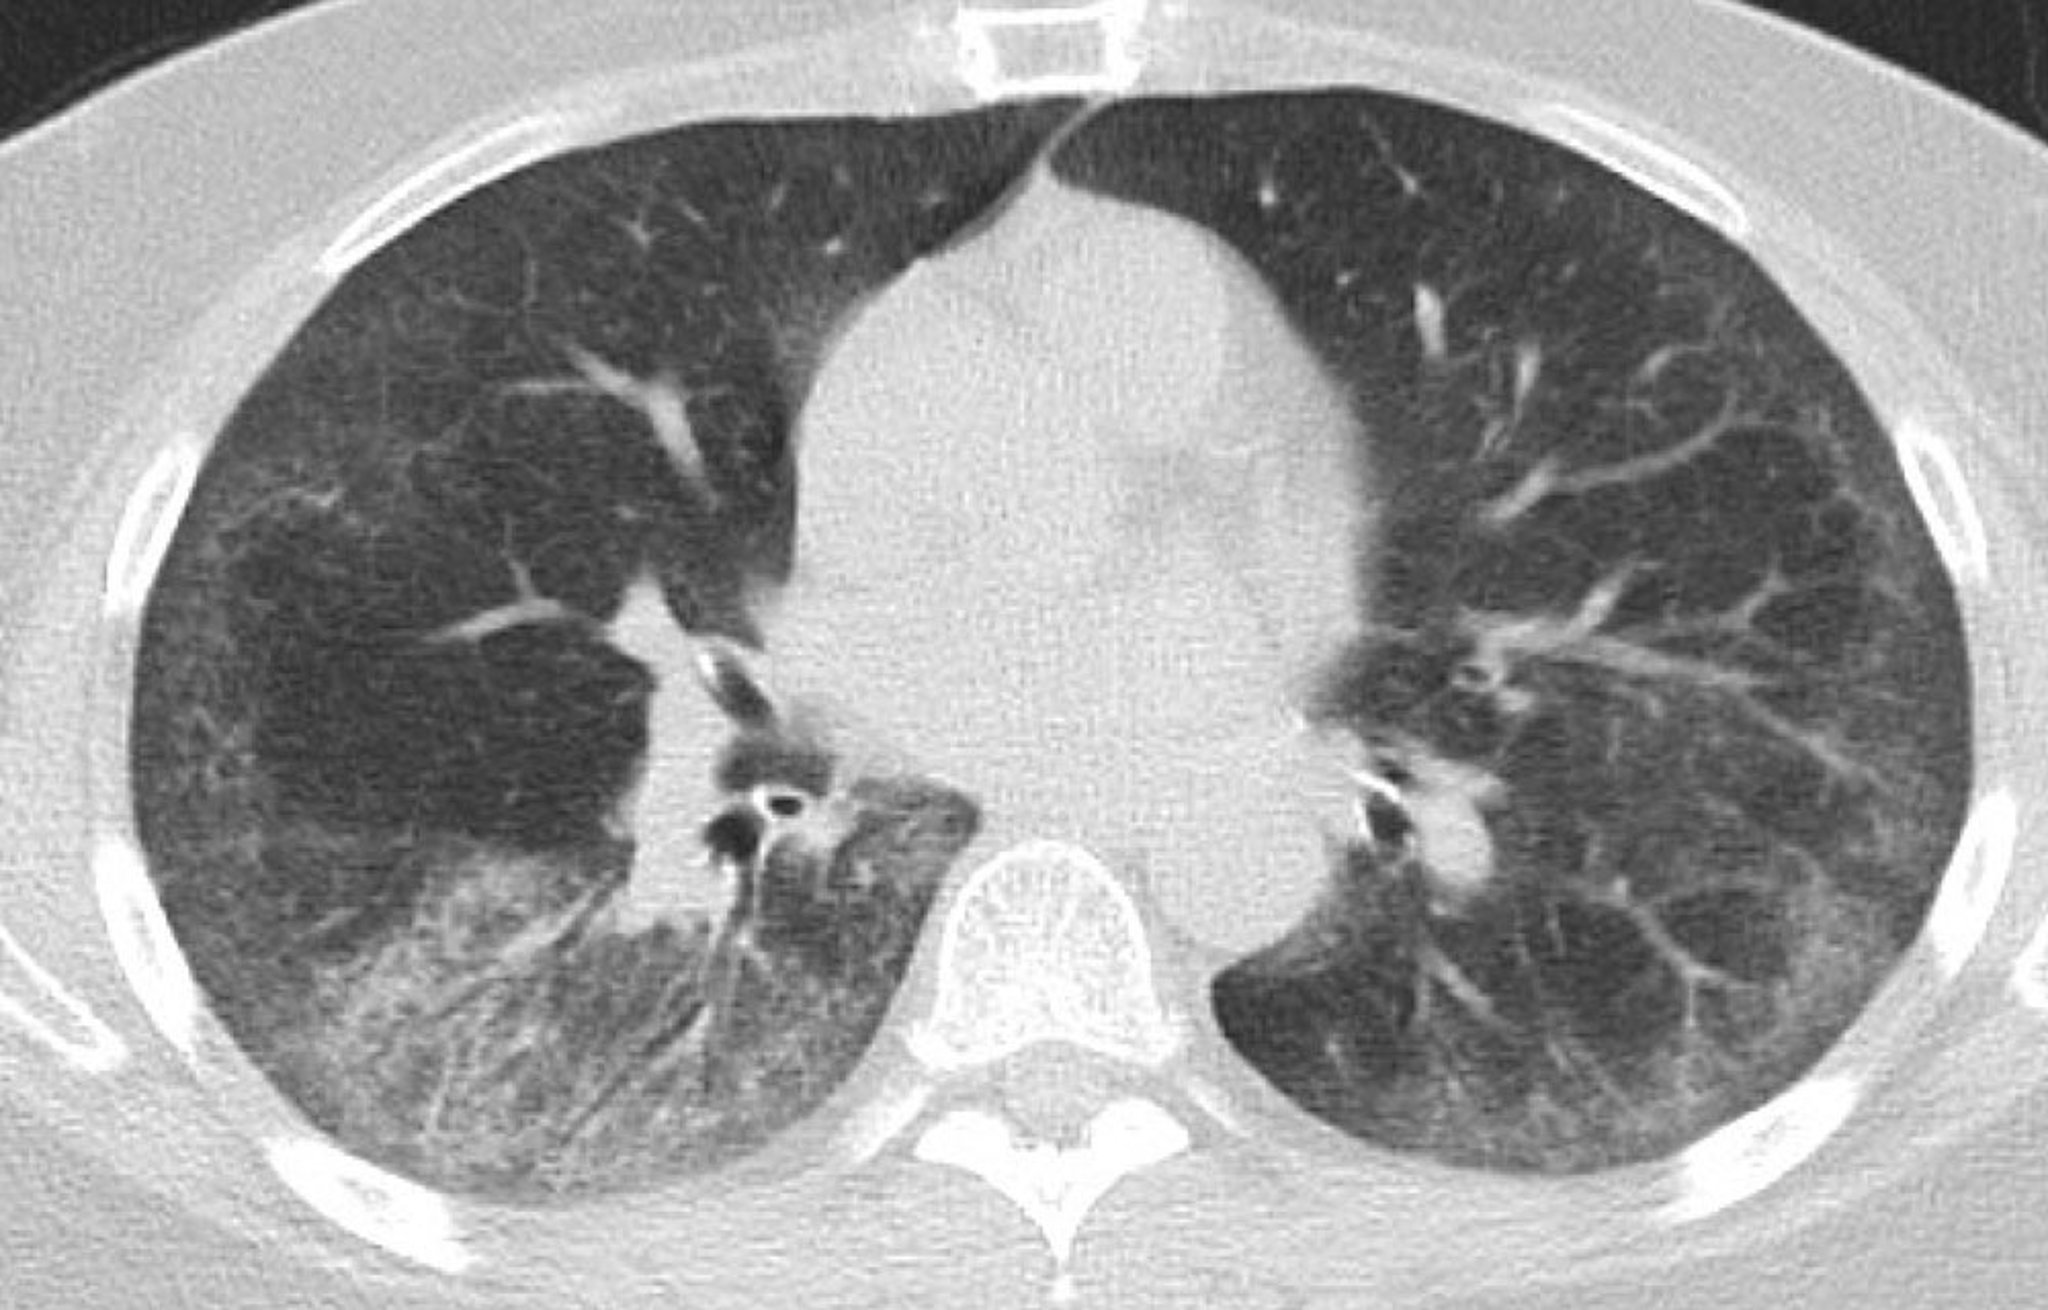

Bệnh phổi kẽ (chụp CT ngực)

Chụp CT cho thấy hình ảnh mờ kính đối xứng, hai bên thùy dưới với các vùng lưới dưới màng phổi mịn; giãn phế quản nhẹ ở cả hai phổi với vùng dưới màng phổi không bị ảnh hưởng; và một vài hạch bạch huyết ngực nằm rải rác.

Hình ảnh do bác sĩ Kinanah Yaseen cung cấp